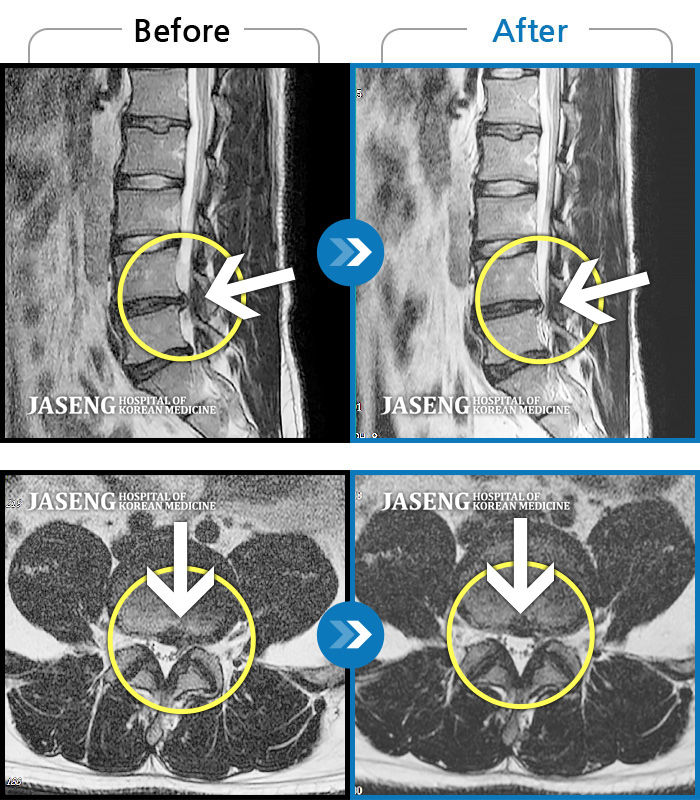

허리디스크

인천 · 강아현 원장

우측 허리 통증 및 다리 저림이 심하여 앉거나 바로 눕는 것도 힘든 상태로 내원하셨습니다. 감각 저하도 동반되어 심각한 신경손상이 의심되는 상황이었습니다.

촬영시기

2024.07.27 ~ 2025.04.05

2025.04.16